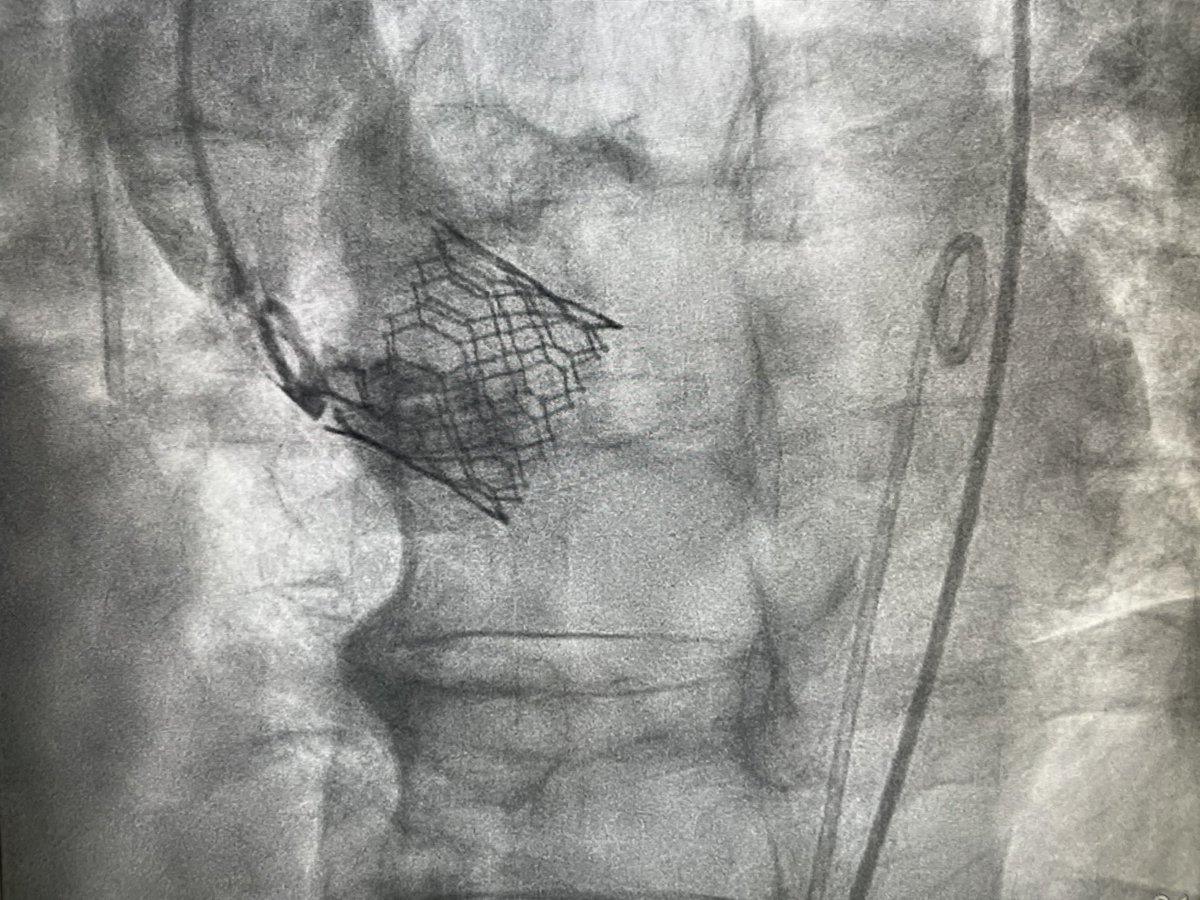

Calcified coronary artery disease pose an important challenge. C2 IVL launched in India. 86 year old gentleman underwent double vessel PCI with #Rotablator and c2#IVL. More pulses for more lesions. #RHL #Jaipur